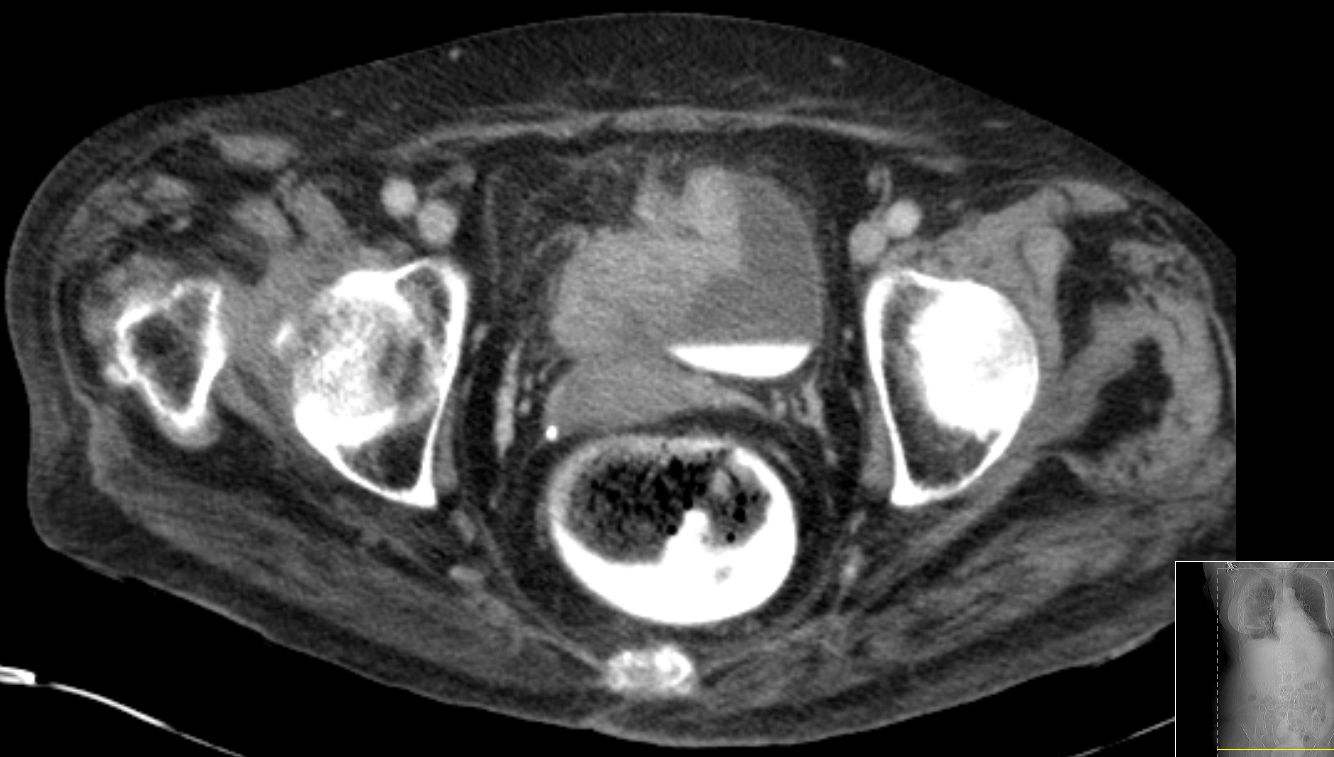

| Rektus - Infiltration | 80-jähriger Mann mit Haematurie seit 6 Monaten.

Endoskopisch ein ausgedehnter Blasentumor gesehen, der von der rechten

Seitenwand zum Dach und der Hinterwand zeiht. Der Tumor war zum Teil solide

infiltrierend wachsend, zum Teil papillär und zerfallen. Eine vollständige

Abtragung war nicht möglich. Das CT zeigte, dass dieser Tumor auch das

anliegende Fettgewebe und den Musculus rectus rechts infiltriert.![]() | |||

Rechts lateral anliegend stellte sich eine 11 mm große

Lymphknotenmetastase dar.![]() |